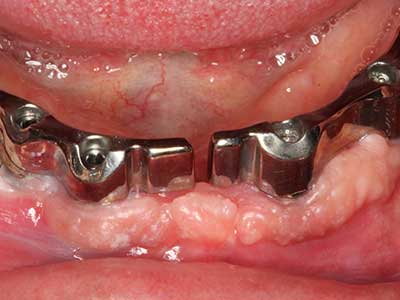

When surgical procedures are performed on bone in the immediate vicinity of sensitive structures such as blood vessels or nerves, rotary instruments pose a significant risk of iatrogenic injury. Piezoelectric devices can be helpful for preparation of bone covers and removal of hard tissue close to nerves, particularly for exposure of nerves after iatrogenic injury but also during nerve lateralization for resective and reconstructive procedures or implant placement (Fig. 17-20). Light contact between the piezotip and the nerve does not generally result in damage but proceeding incautiously with saw-like motions or attachments where a residual bone substrate remains may cause temporary or even permanent nerve damage. However, the risk of damage is considered to be substantially lower than when using saws or milling instruments (Pereira, Gealh et al. 2014).

As shown in the past, basically any bone surgery procedure represents a possible indication for piezo surgery. Thus preparation of the mobile segment in distraction osteogenesis (Fig. 23-25) and sandwich osteotomy uses special attachments without endangering the blood supply to the crestal section, which is essential for the success of both techniques (Gonzalez-Garcia, Diniz-Freitas et al. 2008).

Purely orthodontic indications include orthognathic surgery, genioplasty (Fig. 27-30) and orbital decompression in patients with advanced endocrine orbitopathy as a result of Basedow’s disease (Ponto, Zwiener et al. 2014). Piezo devices are also used in maxillofacial surgery and to remove tumours at the base of the skull in various hospitals.